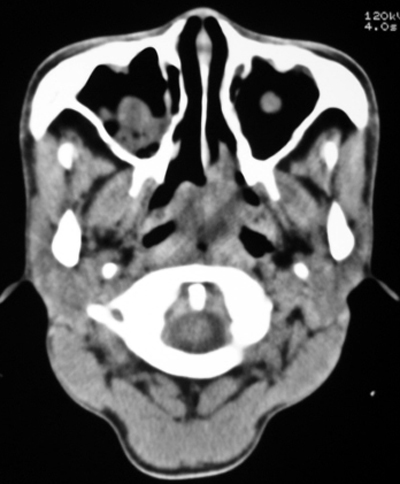

以下是引用bmw011在2009-4-23 13:23:00的发言:[br]考虑鼻息肉,上颌窦、筛窦炎

以下是引用syfszcw在2009-4-23 13:21:00的发言:[br]双侧上颌窦 筛窦慢性炎症,鼻息肉 会厌ca[br][br][本贴已被 syfszcw 于 2009-4-23 13:36:46 修改过]

以下是引用随光逐影在2009-4-23 19:35:00的发言:[br]1)鼻咽、口咽、左侧鼻腔及右侧鼻后孔处新生物,考虑息肉可能性大。2)双侧上颌窦及双侧筛窦炎症,不排除双侧上颌窦内息肉可能。